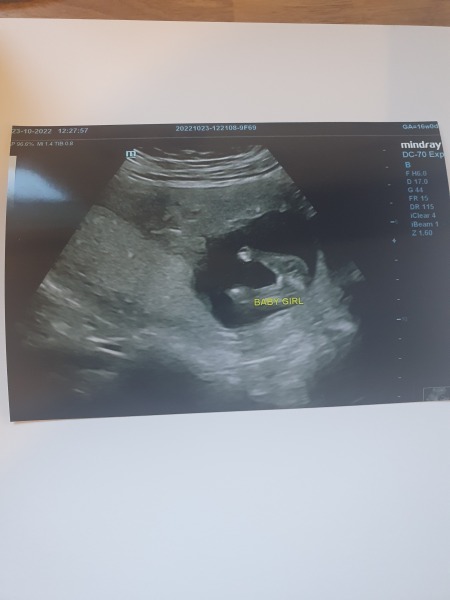

Lisa221987 · 23/10/2022 17:43

Here is our gender reveal at 16 weeks. I hope its right?! We are over the moon its a girl!!!!